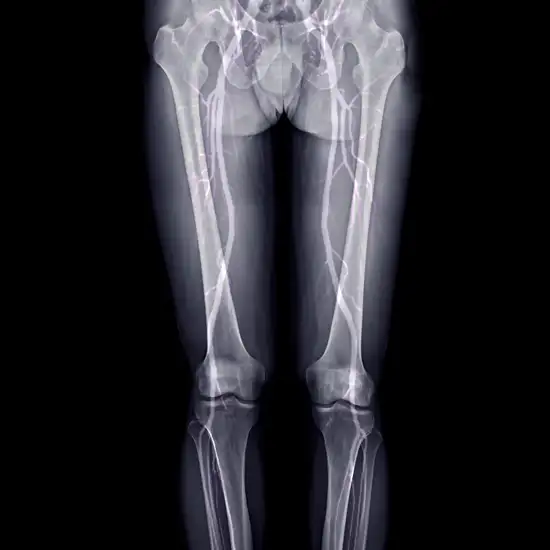

CT Scanogram is a computed tomography scanogram for the lower limb. It is a non-invasive imaging procedure that is performed on patients with suspected inequality in the length of their legs. The doctor prescribes this scan to measure the leg bone length and to find the inequality in the length of the lower limbs. This scan is performed especially on children. In this scan, an X-ray beam and a computer are used to obtain the cross-sectional images of the legs. It is also known as a CT Scanogram for lower limbs.

The CT scanogram test is a digitally acquired X-ray of both lower limbs/legs using digital sensors. This technique creates images of the lower limbs that help in the determination of the length of leg bones and to assess any inequality in the legs.

The CT scanogram images show the pictures of lower limb containing femur bone, tibia bone, patella bone, foot and its bones, and the soft tissue structures associated with these bones.

The standard CT scans create cross-sectional scan images of the body, whereas the CT Scanogram involves producing a two-dimensional scan image pattern of the lower limbs. The CT Scanogram is primarily conducted to outline and locate the regions especially the lower limbs that are used to examine the legs.